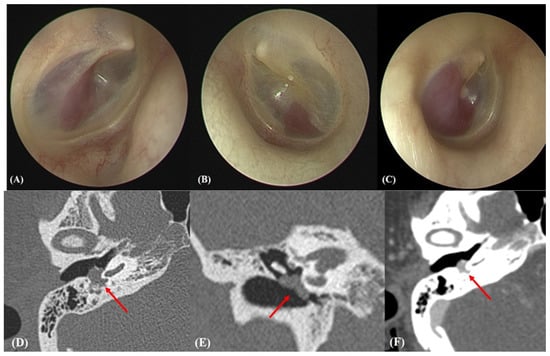

2.2. Otoendoscopic and Radiological Evaluations

3.2. Intraoperative Findings